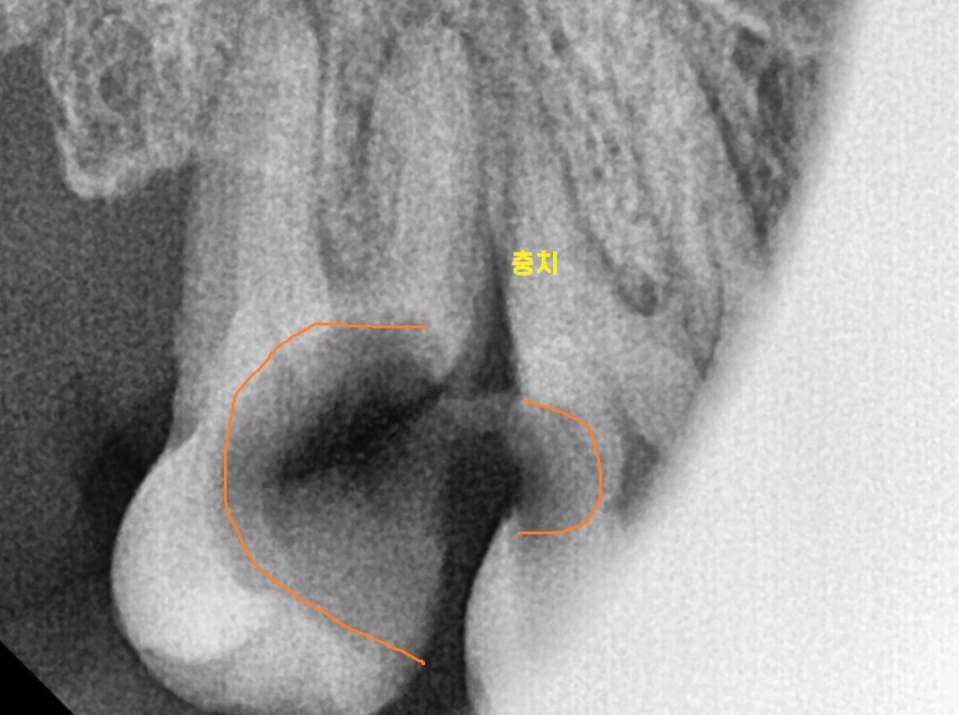

반대로 누워있는 사랑니가

문제를 일으켜 불편하다? 뽑으셔야합니다.

(위에 사진은 사랑니가 뼈 안에 숨어있어요!)

벌어진 잇몸 아래로 음식물이 박혀

냄새가 나고 붓고

앞에 치아에 충치를 일으킬 것 같으면 뽑아야죠~

230725

맨 끝~~에 있어서 관리가 잘 안됐다.

충치가 생겼다.

그러면 뽑아야합니다.

앞에 치아까지 충치가 먹어버렸네요..